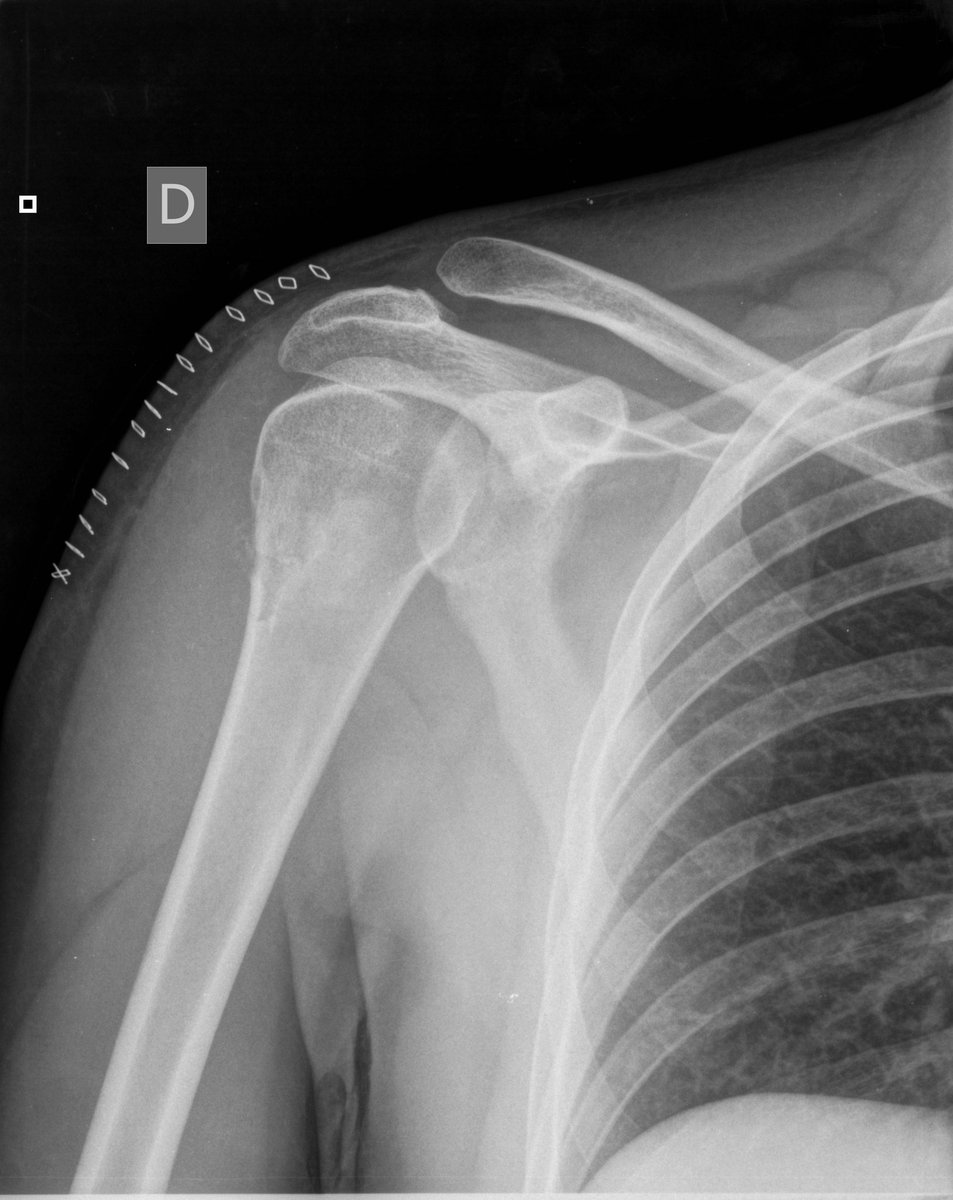

Severe glenohumeral osteoarthritis or jai-alai?

pic.twitter.com/RlMUp5vTnn